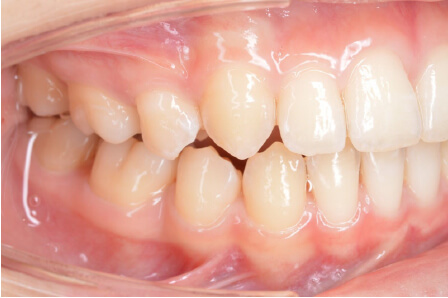

叢生の症例

9歳

男性

相談内容

ガタガタしているのが気になる

カウンセリング・診断結果

叢生。上3.3スペース不足。耳鼻科紹介

治療内容・方法

全額アライナー矯正

術後の経過・現在の様子

リンガルアーチ使用

治療のリスク

痛み・歯根吸収・歯肉退縮・虫歯・後戻り

費用・治療期間

140,800円、1年1ヶ月